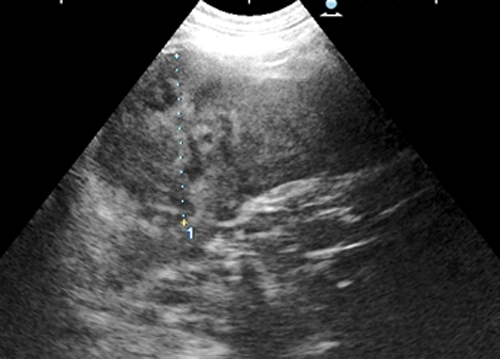

超音波検査

症例:脾臓腫瘍(血管肉腫)